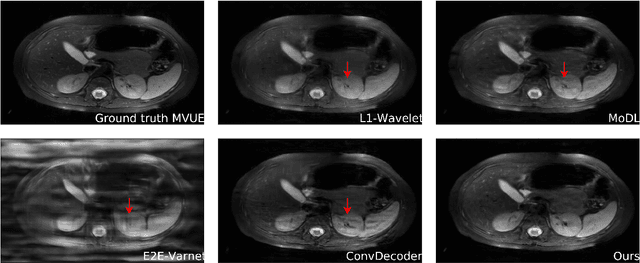

Abstract:Diffusion-based generative models have been used as powerful priors for magnetic resonance imaging (MRI) reconstruction. We present a learning method to optimize sub-sampling patterns for compressed sensing multi-coil MRI that leverages pre-trained diffusion generative models. Crucially, during training we use a single-step reconstruction based on the posterior mean estimate given by the diffusion model and the MRI measurement process. Experiments across varying anatomies, acceleration factors, and pattern types show that sampling operators learned with our method lead to competitive, and in the case of 2D patterns, improved reconstructions compared to baseline patterns. Our method requires as few as five training images to learn effective sampling patterns.

Abstract:Magnetic resonance imaging (MRI) exam protocols consist of multiple contrast-weighted images of the same anatomy to emphasize different tissue properties. Due to the long acquisition times required to collect fully sampled k-space measurements, it is common to only collect a fraction of k-space for some, or all, of the scans and subsequently solve an inverse problem for each contrast to recover the desired image from sub-sampled measurements. Recently, there has been a push to further accelerate MRI exams using data-driven priors, and generative models in particular, to regularize the ill-posed inverse problem of image reconstruction. These methods have shown promising improvements over classical methods. However, many of the approaches neglect the multi-contrast nature of clinical MRI exams and treat each scan as an independent reconstruction. In this work we show that by learning a joint Bayesian prior over multi-contrast data with a score-based generative model we are able to leverage the underlying structure between multi-contrast images and thus improve image reconstruction fidelity over generative models that only reconstruct images of a single contrast.

Abstract:Magnetic Resonance Imaging (MRI) is a powerful medical imaging modality, but unfortunately suffers from long scan times which, aside from increasing operational costs, can lead to image artifacts due to patient motion. Motion during the acquisition leads to inconsistencies in measured data that manifest as blurring and ghosting if unaccounted for in the image reconstruction process. Various deep learning based reconstruction techniques have been proposed which decrease scan time by reducing the number of measurements needed for a high fidelity reconstructed image. Additionally, deep learning has been used to correct motion using end-to-end techniques. This, however, increases susceptibility to distribution shifts at test time (sampling pattern, motion level). In this work we propose a framework for jointly reconstructing highly sub-sampled MRI data while estimating patient motion using score-based generative models. Our method does not make specific assumptions on the sampling trajectory or motion pattern at training time and thus can be flexibly applied to various types of measurement models and patient motion. We demonstrate our framework on retrospectively accelerated 2D brain MRI corrupted by rigid motion.

Abstract:The CSGM framework (Bora-Jalal-Price-Dimakis'17) has shown that deep generative priors can be powerful tools for solving inverse problems. However, to date this framework has been empirically successful only on certain datasets (for example, human faces and MNIST digits), and it is known to perform poorly on out-of-distribution samples. In this paper, we present the first successful application of the CSGM framework on clinical MRI data. We train a generative prior on brain scans from the fastMRI dataset, and show that posterior sampling via Langevin dynamics achieves high quality reconstructions. Furthermore, our experiments and theory show that posterior sampling is robust to changes in the ground-truth distribution and measurement process. Our code and models are available at: \url{https://github.com/utcsilab/csgm-mri-langevin}.